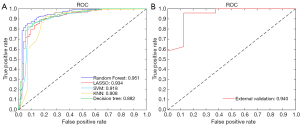

In the internal validation, the area under the receiver operating characteristic (ROC) curve (AUC), accuracy, specificity, and sensitivity were generated after each run of the ten-fold CV. The mean values of the ten runs were recorded to measure the overall performance of our ML models. The predictive power of the best-performing ML algorithm was determined in the internal validation and was further verified by our independent external validation dataset. The flowchart is shown in Figure 2.

A series of true positive rates (TPR) and false positive rates (FPR) were obtained to form the ROC curves. TPR is also known as sensitivity, while FPR is defined as subtracting the specificity value from 1. The AUC was calculated as the area between the ROC and the FPR axis. The optimal cut-off point was obtained using the highest Youden’s index (sensitivity + specificity − 1), and the corresponding optimal sensitivity and specificity values were recorded. The overall accuracy and AUC in internal validation were presented as the mean and the 95% confidence interval (CI). The ML models were established and evaluated by MATLAB (version 9.5.0.9; MathWorks).

In the internal validation, the mean AUCs of the five ML algorithms were 0.882–0.951 (95% CI: 0.789–0.993), with mean accuracies of 0.857–0.892 (95% CI: 0.812–0.940), mean sensitivities of 0.865–0.934 (95% CI: 0.805–0.970), and mean specificities of 0.804–0.973 (95% CI: 0.659–1.000). Among these ML algorithms, RF achieved the best performance. The mean AUC of RF was 0.951 (95% CI: 0.908–0.993), with a mean accuracy of 0.892 (95% CI: 0.844–0.940), a mean sensitivity of 0.904 (95% CI: 0.856–0.952), and a mean specificity of 0.973 (95% CI: 0.938–1.000). The performance metrics of the ML algorithms are shown in Table 2, and the comparison among ROC curves is presented in Figure 3A.

In the external validation, the AUC obtained by the RF algorithm was 0.940, with an accuracy of 0.875, a sensitivity of 0.875, and a specificity of 0.958 (Table 2 and Figure 3B). Furthermore, our best-performing model (i.e., RF algorithm) identified BASE as the most critical parameter for the accurate prediction of postoperative IMH status (Figure 4). To better illustrate the importance of BASE, binary logistic regression analysis was derived for prediction of IMH status using BASE in internal validation set. The ROC curve of BASE was showed in Figure 5, with an AUC of 0.911.

In the present study, five ML algorithms were trained and evaluated to predict IMH status after standard VILMP surgery. The RF algorithm (i.e., the best-performing algorithm) was further validated using an independent external validation set. In our study, the best-performing ML algorithm provided promising predictions with an AUC of 0.951 in the training and internal validation set and an AUC of 0.940 in the external validation set, suggesting its encouraging capability of accurately predicting IMH status (i.e., closed or open) after VILMP based on preoperative OCT features and clinical variables. Moreover, we identified that BASE is the most critical feature for an accurate prediction.